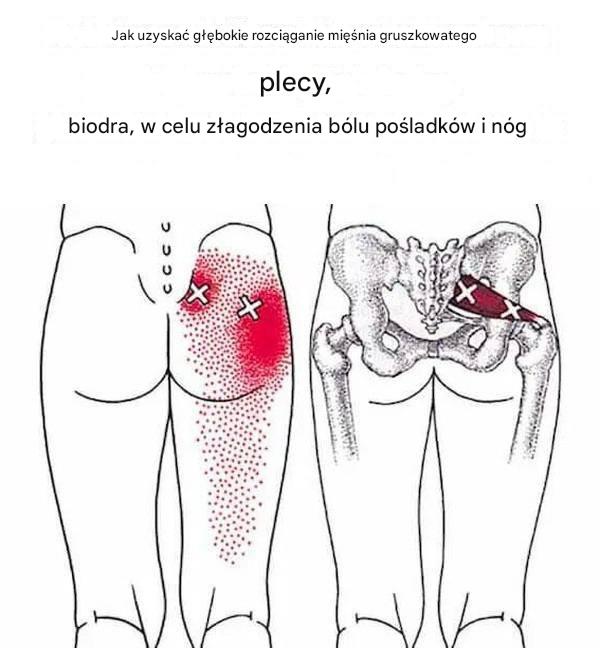

Jak rozciągnąć głęboko mięsień gruszkowaty, aby wyeliminować ból pleców, bioder, pośladków i nóg

Ból dolnej części pleców jest bardzo powszechny i może mieć wiele przyczyn. Jedna z nich zazwyczaj nie jest pierwszą podejrzewaną przyczyną, ale występuje częściej,…